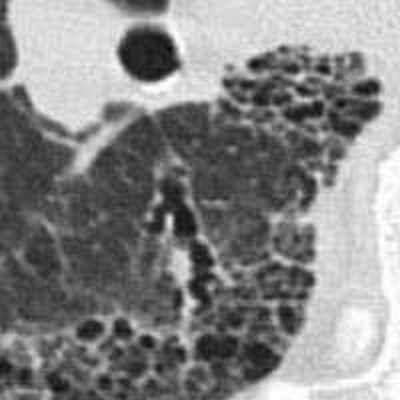

«Матовые стекла» — это участки уплотнения легочной ткани, которые хуже пропускают X-Ray лучи. По-другому их называют очагами уплотнения ткани легких. На томограммах такие области напоминают светлые пятна или мутноватый налет. Очаги по типу «матового стекла» свидетельствуют о том, что альвеолы легких заполнены жидкостью (транссудатом, кровью), а не воздухом. Также они могут свидетельствовать о снижении пневматизации легких из-за фиброзных изменений. Альвеолы участвуют в газообмене, снабжают клетки кислородом и выводят углекислый газ, поэтому заполнение их полости жидким веществом или клетками соединительной ткани недопустимо.

Оценивая данные КТ легких, врач-рентгенолог дифференцирует заболевания по специфической картине «матовых стекол»: их количеству, локализации, наличию других признаков, по которым возможно определить причину патологических изменений ткани легких. Например, для двусторонней вирусной пневмонии характерно наличие «матовых стекол», расположенных периферически в нижних и задних отделах легких. В более поздней стадии наблюдается консолидация очагов инфильтрации с утолщением перегородок альвеол.

«Матовые стекла» при туберкулезе могут быть расположены рядом с бронхами или диссеминированы — в этом случае наблюдается множество маленьких светлых участков (инфильтратов), хаотично расположенных во всей полости легких. Также при туберкулезе на КТ легких можно обнаружить характерные фиброзные тяжи, ведущие к корню легкого — это перибронхиальное воспаление, признаки лимфостаза с увеличением лимфатических узлов. Единичные участки «матового стекла» малого размера без четкого паттерна какого-либо заболевания могут указывать на новообразование, развивающийся фиброз, аденокарциному (рак) легких.

Опухоль аденокарцинома формируется из клеток железистого эпителия. На томограмме представлена единичным обычно небольшим (от 2 мм) участком уплотнения по типу «матового стекла». В отдельных случаях у пациента наблюдается несколько «матовых стекол» диффузного или диффузно-мозаичного типа. Аденокарцинома представлена различными морфологическими подтипами и требует динамического наблюдения.